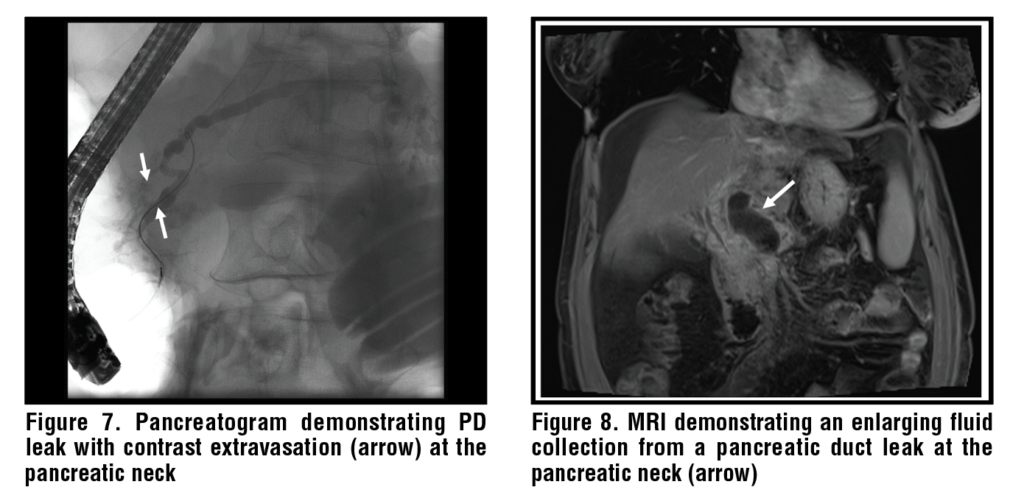

Accurate identification and characterization of PD disruption is important in guiding the approach to management. Currently, there are no consensus guidelines for the diagnosis of PD leaks. ERCP is traditionally considered the gold standard for confirming the presence, severity, and site of PD disruption, which is defined by contrast extravasation from the pancreatic ductal system. (See Figures 5-7.) The potential for ERCP to cause pancreatitis and superinfection, and the improvement in noninvasive imaging modalities, has resulted in ERCP being primarily reserved for cases where endotherapy is warranted in the setting of a diagnostic evaluation.21 Generally, the diagnostic approach is determined by the clinical presentation.

In the setting of acute pancreatitis, contrast-enhanced computerized tomography (CT) is often obtained as part of the initial diagnostic workup. Clinical worsening should prompt repeat CT imaging to evaluate for the development of PFCs and pancreatic necrosis. Identification of a PFC suggests that a PD leak is present, and its location may suggest the site of PD disruption. (See Figure 8.) Serial imaging demonstrating a persistent or enlarging PFC further supports the presence of an ongoing PD leak, which can be confirmed with magnetic resonance cholangiopancreatography (MRCP), secretin-enhanced MRCP (S-MRCP), or ERCP. In the setting of DPDS, S-MRCP has high sensitivity for identifying the site of ductal disruption and may additionally visualize the disconnected portion of the pancreas.22 In the setting of chronic pancreatitis, CT is often used in the initial diagnosis of chronic pancreatitis and to evaluate for calcified PD stones, PD strictures, and sequelae of PD leaks in the case of symptom progression.23

Transpapillary drainage involves an ERCP with insertion of a PD stent that bridges the site of PD disruption. (See Figures 11-13.) Bridging the site of PD disruption with a PD stent promotes physiological flow of pancreatic fluid into the duodenum rather than through the site of PD disruption and correlates with successful outcomes.24,25 Additionally, PD stents can be used to bypass areas of ductal obstruction due to PD stones and strictures. The stent diameter depends on the PD diameter and should not exceed the diameter of the upstream PD.26 While pancreatic sphincterotomy is not required for stent insertion, it can be used to facilitate stone extraction and PD stricture dilation and is often performed if the need for repeated PD access is anticipated in the future. Optimal stent duration/indwell time is unclear and depends on the etiology of the PD leak and operator preference. In cases where the upstream portion of the PD is unable to be accessed, a shorter stent can be placed, with a plan to re-attempt ERCP to bridge the leak at a later date. In most case series, PD stents were left in place for 4-8 weeks with shorter durations being associated with an increased risk of recurrence or failure and longer durations being associated with stent occlusion and ductal changes in a previously otherwise normal PDs, but this has not been universally reported.24,25,27–29 Importantly, many patients need, and tolerate, long PD stent indwell times without any evidence of duct injury. Lastly, transpapillary drainage can be used to drain PFCs that communicate directly with the main PD. This technique involves placing the distal aspect of the stent directly into the PFC and is supported by case-series that have demonstrated its effectiveness, though it is not the preferred route of drainage.30,31 (See Figure 14.) Even if the PD does not clearly communicate with the PFC, a PD stent can still help to prevent backfilling of the PFC and can promote resolution.